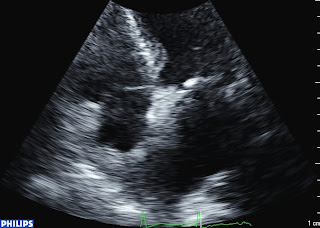

En ETT, on note sur la paroi laterale de l’OD une masse peu mobile et hyperéchogène:

Cette masse envahie tous le septum inter auriculaire, et ne prend pas le contraste après injection de micro-bulles:

En ETO, le septum inter auriculaire est pris en masse et mesure jusqu’à 3 cm. Cette infiltration est hyperechogène, régulière, et respecte la fosse ovale.